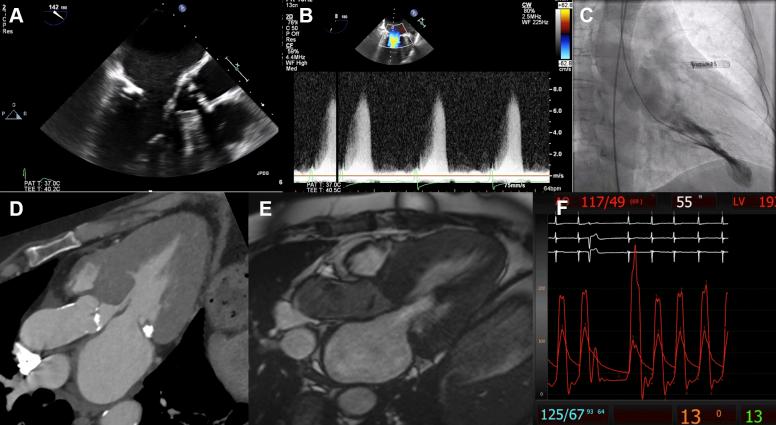

Patients with aortic stenosis and concomitant left ventricular outflow tract obstruction undergoing transcatheter aortic valve replacement are at risk of hemodynamic collapse after the procedure due to worsening left ventricular outflow tract obstruction. We present 3 cases highlighting the important interplay between these 2 disease states and associated diagnostic and treatment challenges. ().

患有主动脉瓣狭窄并伴有左心室流出道梗阻的患者在接受经导管主动脉瓣置换术后,由于左心室流出道梗阻加重,有发生血流动力学崩溃的风险。我们介绍3例病例,突出这两种疾病状态之间重要的相互作用以及相关的诊断和治疗挑战。()